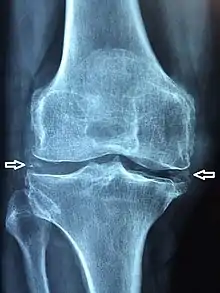

X-ray, CT, or other imaging usually shows accumulation of calcium within the joint cartilage, known as chondrocalcinosis. There can also be findings of osteoarthritis.[5][4] The white blood cell count is often raised.[4]

Medical imaging, consisting of x-ray, CT, MRI, or ultrasound may detect chondrocalcinosis within the affected joint, indicating a substantial amount of calcium crystal deposition within the cartilage or ligaments.[2] Ultrasound is a reliable method to diagnose CPPD.[8] Using ultrasound, chondrocalcinosis may be depicted as echogenic foci with no acoustic shadow within the hyaline cartilage[9] or fibrocartilage.[8] By x-ray, CPPD can appear similar to other diseases such as ankylosing spondylitis and gout.[2][4]

Arthrocentesis, or removing synovial fluid from the affected joint, is performed to test the synovial fluid for the calcium pyrophosphate crystals that are present in CPPD. When stained with H&E stain, calcium pyrophosphate crystals appears deeply blue ("basophilic").[10][11] However, CPP crystals are much better known for their rhomboid shape and weak positive birefringence on polarized light microscopy, and this method remains the most reliable method of identifying the crystals under the microscope.[12] However, even this method has poor sensitivity, specificity, and inter-operator agreement.[12]

Calcium pyrophosphate dihydrate crystals are associated with a range of clinical syndromes, which have been given various names, based upon which clinical symptoms or radiographic findings are most prominent.[13] A task force of the European League Against Rheumatism (EULAR) made recommendations on preferred terminology.[6] Accordingly, calcium pyrophosphate deposition (CPPD) is an umbrella term for the various clinical subsets, whose naming reflects an emphasis on particular features. For example, pseudogout refers to the acute symptoms of joint inflammation or synovitis: red, tender, and swollen joints that may resemble gouty arthritis (a similar condition in which monosodium urate crystals are deposited within the joints). Chondrocalcinosis,[2][4] on the other hand, refers to the radiographic evidence of calcification in hyaline and/or fibrocartilage. "Osteoarthritis (OA) with CPPD" reflects a situation where osteoarthritis features are the most apparent. Pyrophosphate arthropathy refers to several of these situations.[17]